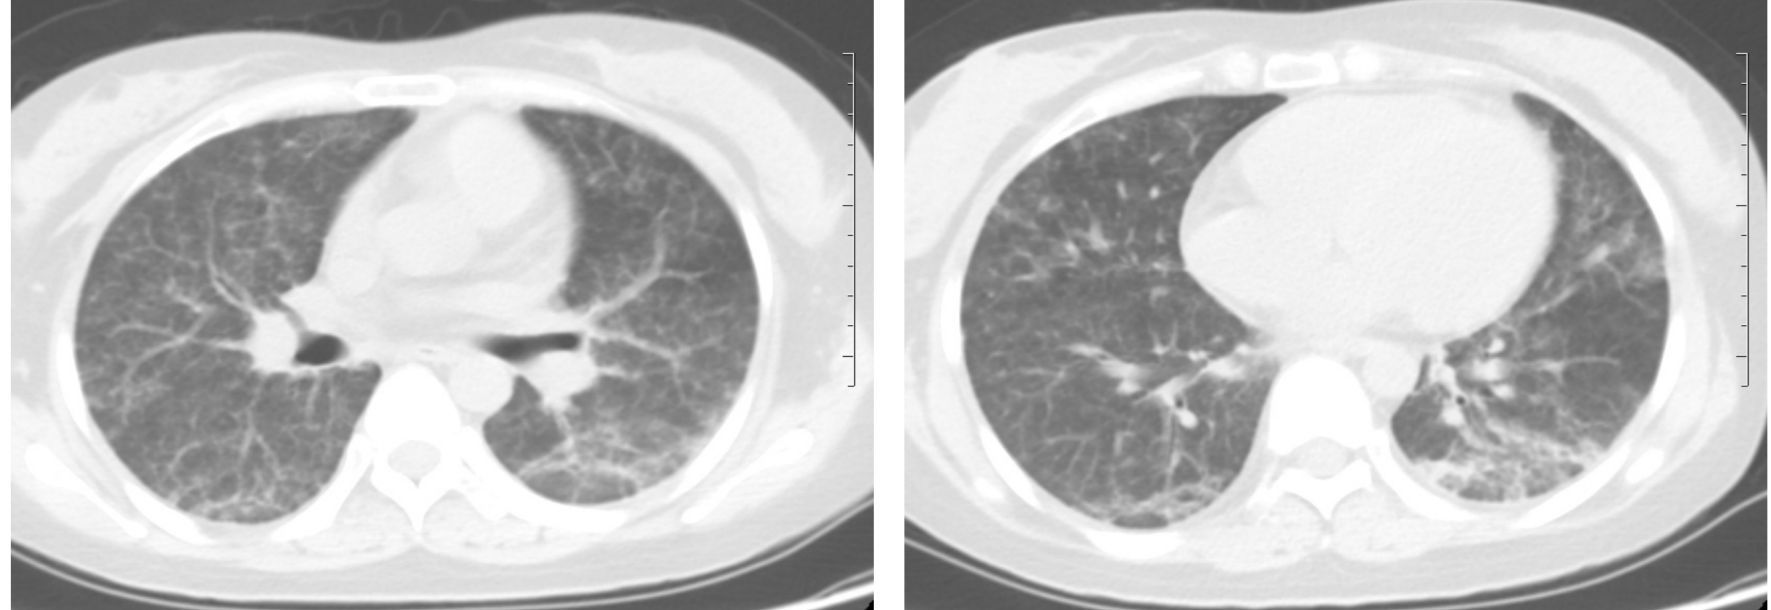

患者,女,24岁,主因“发热、干咳20余天”入院。外院抗生素治疗效果差。既往肾病综合征,口服激素。查体:T 38 ℃、P 105次/min,RR 20次/min,BP 102/73 mmHg(1 mmHg=0.133 kPa),双肺未闻及啰音。辅助检查:WBC 1.52× 109 L-1、NE 78.3%;CRP 71 mg/L;ALT 248 U/L、AST 118 U/L;动脉血气(未吸氧):pH 7.44,PaCO2 34 mmHg,PaO2 69 mmHg;胸部平片未见异常。入院后美罗培南治疗3 d,未见好转,呼吸困难进行性加重,I型呼吸衰竭。第3日胸部CT提示双肺间质弥漫渗出,部分实变(图 1),病原不明确,调整抗感染方案:美罗培南、莫西沙星、磺胺、卡泊芬净、更昔洛韦250 mg/12 h、甲强龙40 mg/d、丙种球蛋白。第6日症状明显好转,复查胸部CT较前明显吸收(图 2),此时回报PCT、血培养、G试验、GM试验、呼吸道病原菌培养均阴性;CD4、CD8及CD4/CD8显著下降;肺泡灌洗液CMV-DNA 9.4×105 拷贝/mL,血清CMV-DNA 4.35×104 拷贝/mL,考虑巨细胞病毒肺炎诊断明确,维持更昔洛韦、甲强龙治疗3周,1月后胸部CT示渗出及实变完全吸收(如图 3)。

图 1 第3日胸部CT